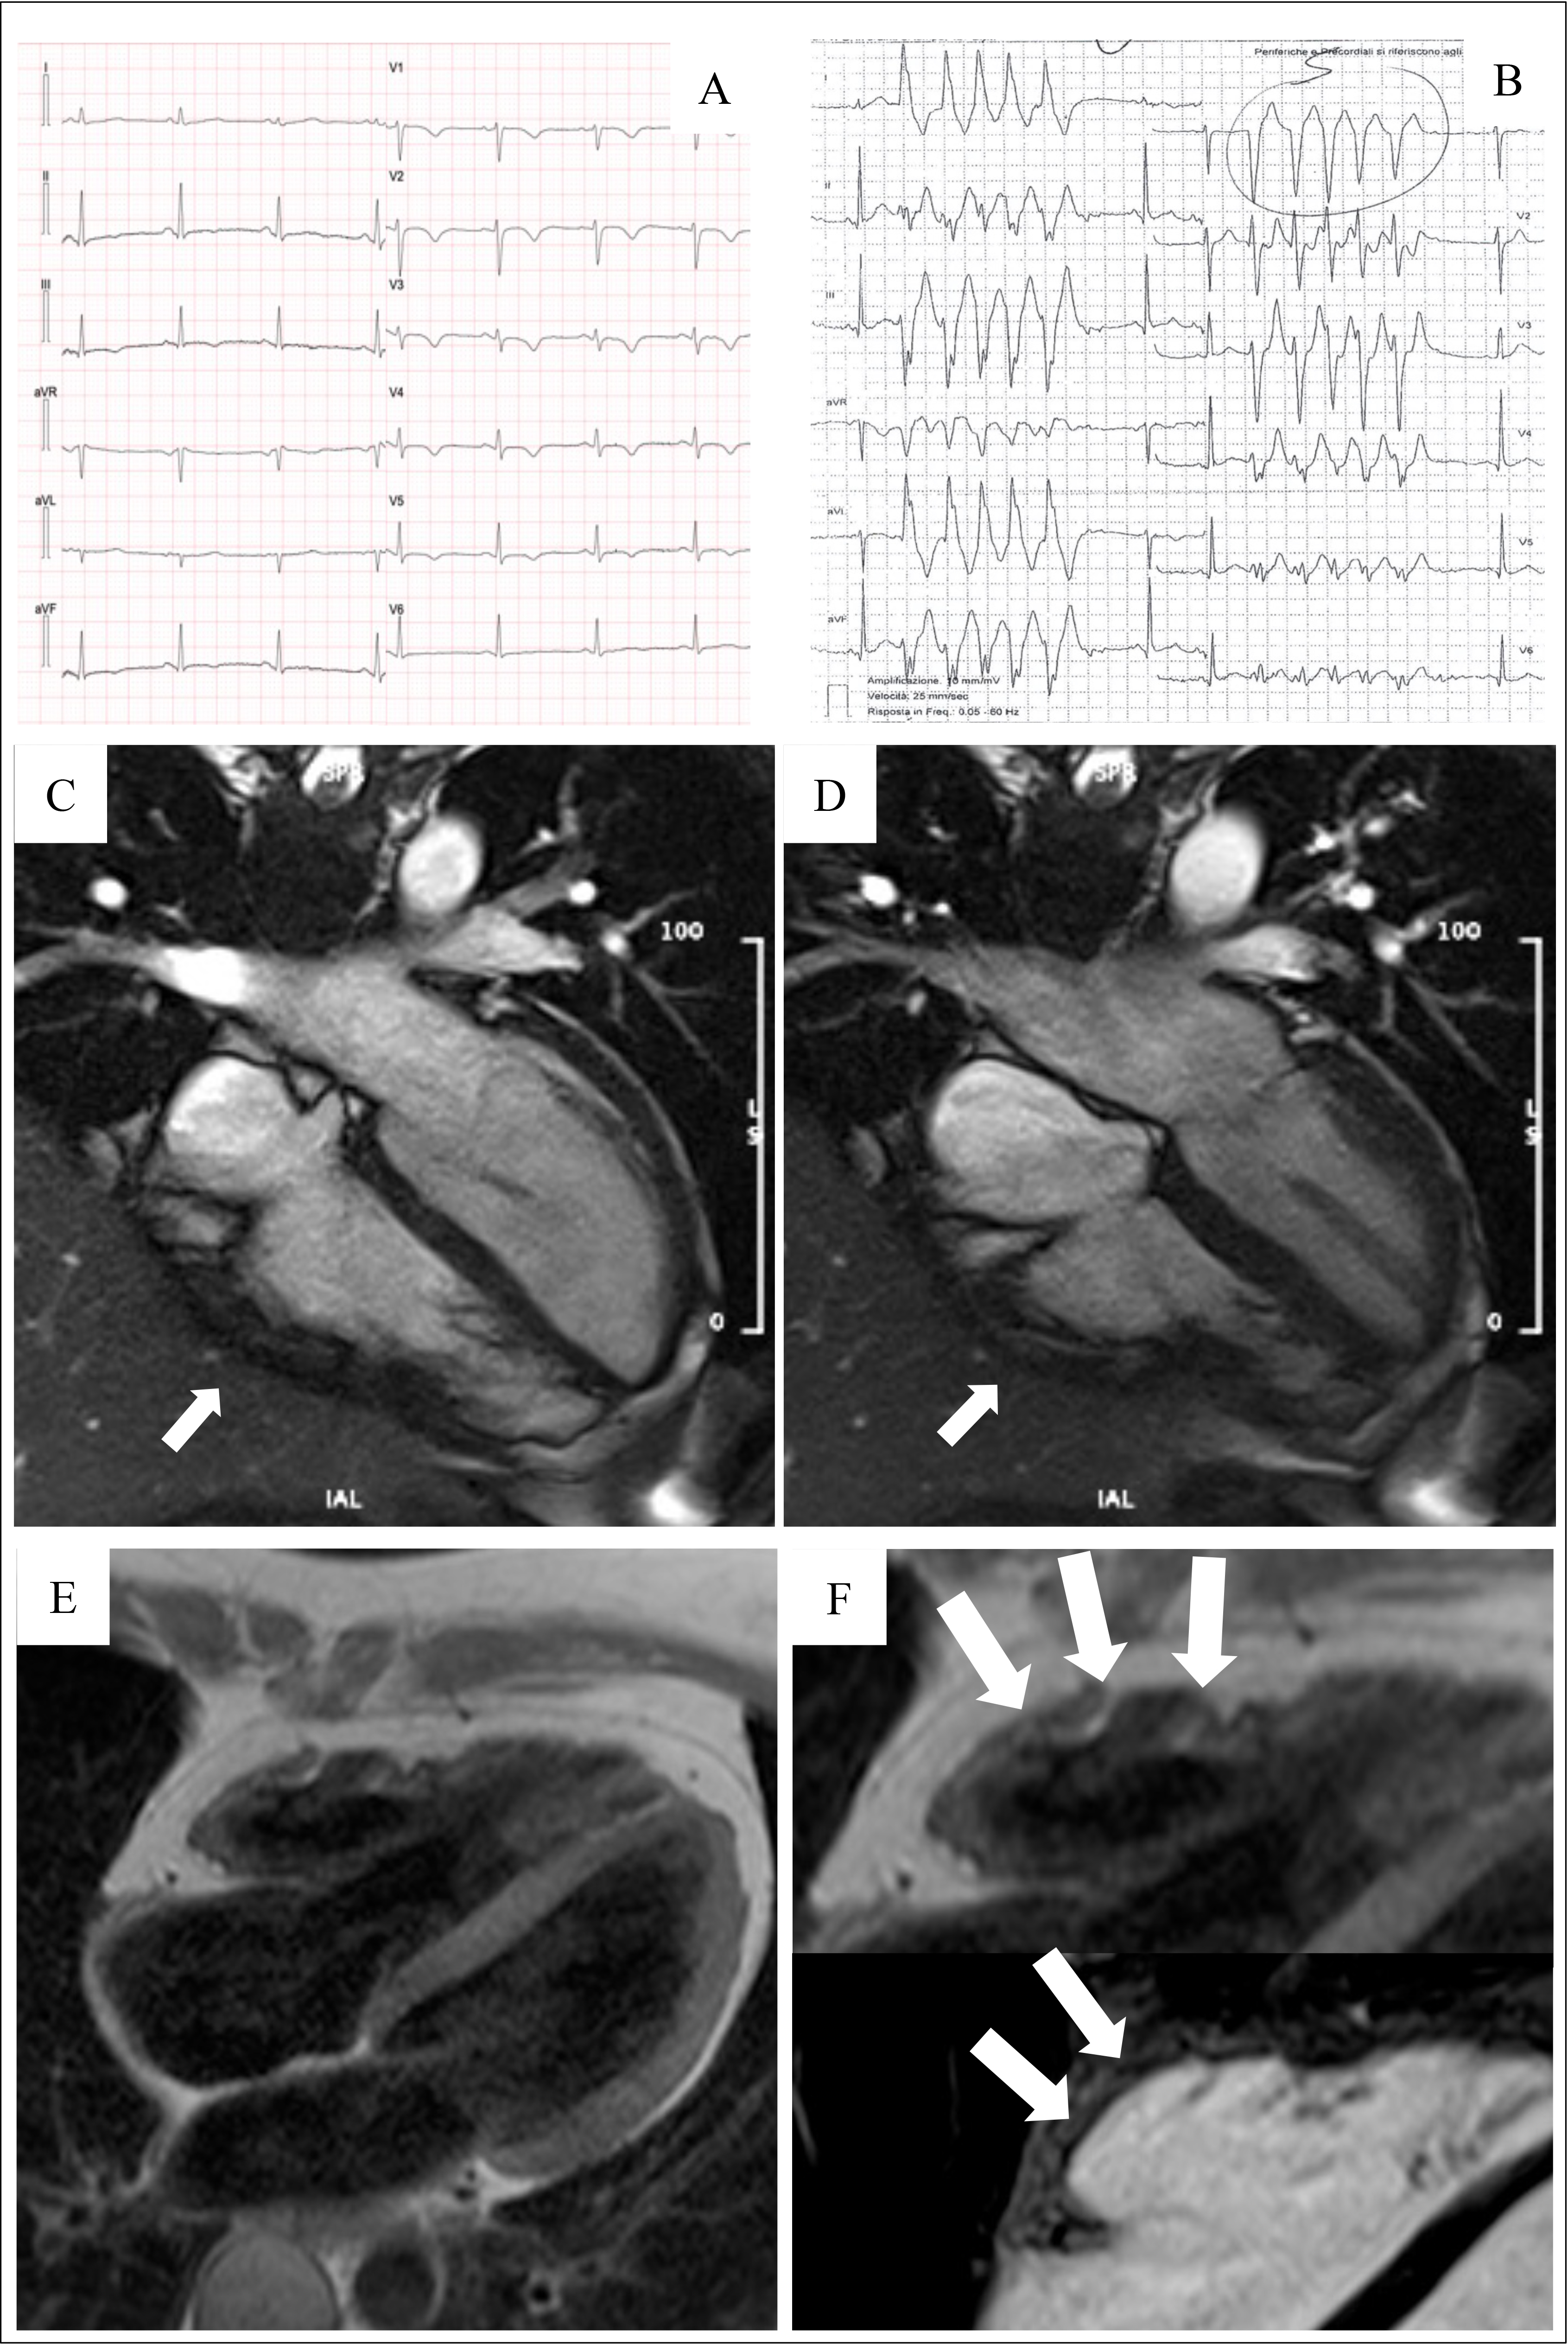

The introduction of non-invasive tissue characterization with CMR is one of the most important innovations of the 2020 criteria. The major CMR criterion is the presence of transmural LGE in at least 1 RV segment, confirmed in 2 orthogonal views. Currently, the diagnostic specificity of RV LGE is considered high, instead the sensitivity is low. This is due to the CMR technology characterized by a poor spectral resolution and suboptimal contrast/noise ratio in quantifying the thin RV wall [17, 28, 29, 30]. The highest specificity is reached when wall motion abnormalities and pre/post contrast signal alterations are considered together [29] (Fig. 3, Ref. [31]).

Fig. 3.Clinical features of ARVC. Basal ECG, exercise testing ECG and CMR findings in a 38-year-old woman hospitalized for sustained VT. Basal ECG showed TWI in V1–V5 and flattened T wave in inferior leads (A). Exercise testing revealed frequent PVBs and a non-sustained VT with LBBB/superior axis morphology, originating from RV free wall (B). CMR revealed mild RV dilatation, moderate RV systolic disfunction, a wide peritricuspid aneurysm, with an extreme thinning of the wall (four-chamber cine view in diastolic phase, C, and systolic phase, D). The PD-TSE sequences revealed fatty infiltration of the RV wall, especially in the subtricuspid region (E, and magnified on the top of F). No RV LGE was identified, not even in the same regions of RV fatty infiltration, maybe because an extreme thinning of the RV wall (F on the bottom). The diagnosis was “definite ARVC”. ARVC, arrhythmogenic right ventricular cardiomyopathy; CMR, cardiac magnetic resonance; LBBB, left bundle branch block; LGE, late gadolinium enhancement; PD-TSE, positron density-turbo spin echo; PVBs, premature ventricular beats; RV, right ventricle; TWI, T wave inversion; VT, ventricular tachycardia. Adapted from Graziano et al. [31].